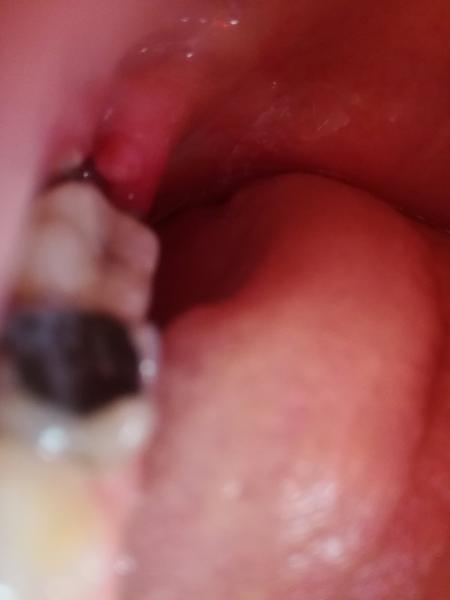

priložená fotografia je dosť neostrá a ťažko podľa nej súdiť stav, ale čo sa farby týka, tak okolie extrakčnej rany nevykazuje známky výrazného zápalu, nebadám opuch, bielo-šedý povlak v hojacej sa rane po vytiahnutí zubu je takzvaný fibrín, ktorý vzniká z krvnej zrazeniny a predstavuje normálny priebeh hojenia.

Po vytiahnutí dolného zubu múdrosti zostáva veľká rana, ktorá sa dlho hojí, tento obraz na 5. deň mi príde primeraný, k úplnému uzavretiu rany dochádza približne po 3 týždňoch od vytiahnutia zubu a samotné hojenie kosti trvá viacero mesiacov. Opuch po ťahaní zubu je bežný, predsa len, jedná sa o chirurgický zákrok.